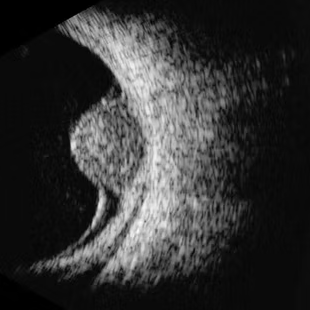

Ecografía modo B (B-Scan o bidimensional):

Genera imágenes en 2D (como un corte del ojo) y videos en tiempo real.

Es el más utilizado para visualizar la anatomía interna: retina, vítreo, coroides, esclerótica, etc.

Permite detectar patologías como desprendimientos, masas tumorales o hemorragias.